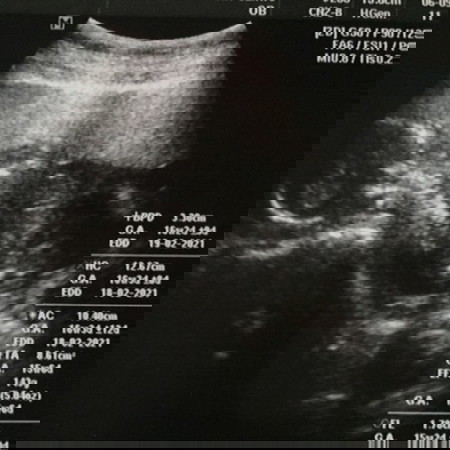

มีใครดูออกไหมว่าหญิงรึชาย 16week

ภาพนี้เป็นภาพศีรษะและกระดูกสันหลังค่ะ มองไม่เห็นนะคะ ต้องเป็นภาพที่ถ่ายช่วงต้นขา แม่มีภาพอื่นอีกไหมคะ